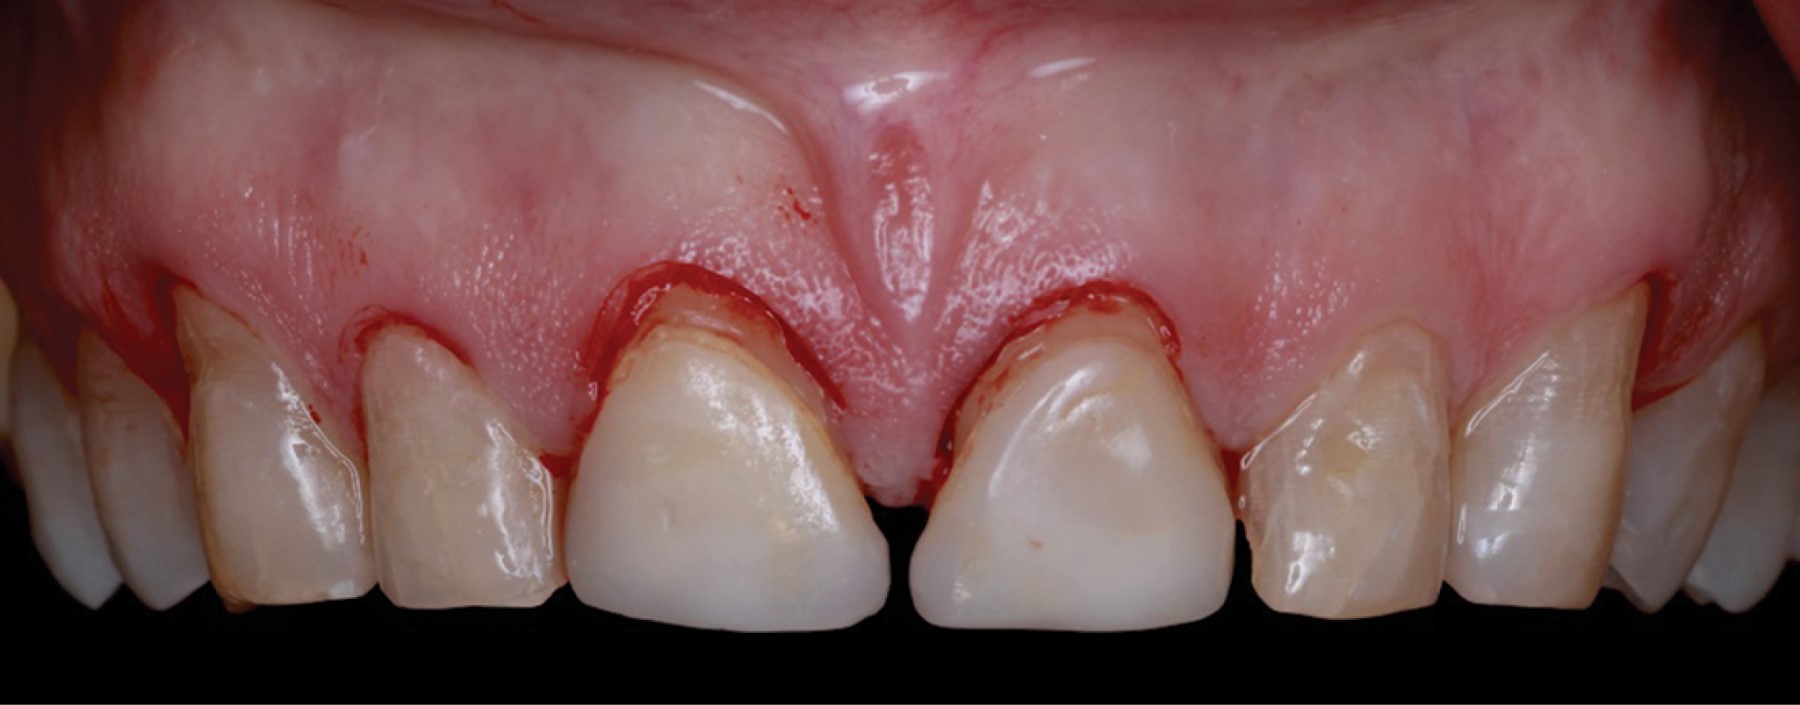

Introduction: crown lengthening for aesthetic purposes aims to reveal an adequate crown length and reduce gingival exposure. The procedure includes gingivectomy and alveolectomy to restore the prosthetically required supracrestal gingival tissue according to physiological dimensions. Through an intraoral scan of the maxilla, mandible, and maximum intercuspidal position, and using specialized software, the shape of the teeth and the gingival contour are digitally designed. This design generates an image of the desired aesthetic restoration for the prosthodontist and periodontist. The physical fabrication of the design is computer-assisted (CAD-CAM), creating a vacuum-formed acrylic resin surgical guide to determine the clinical crown length required in surgery. Objective: the presented interdisciplinary case describes an innovative technique using digital workflow through software that, from an oral scan, digitally designs a Mock-Up used as a guide for periodontal surgery. Case presentation: a 52-year-old ASA I patient attended the Periodontics Master's clinic at Universidad Autónoma de Coahuila (UAdeC) for periodontal surgery with aesthetic purposes. The surgery was performed by placing the Mock-Up in the anterosuperior region as a guide for gingivectomy. Then, a flap was raised before the alveolectomy, considering the length of the supracrestal gingival tissue. Finally, the soft tissues were sutured with a horizontal mattress suture technique. Results: seven days later, the sutures were removed, showing correct and uniform tissue healing. Conclusions: this digital approach offers a significant reduction in surgical time, in addition to satisfactory esthetics and precise gingival architecture.

Figure 3